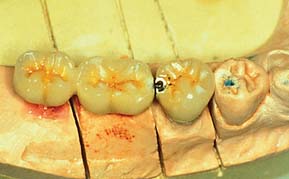

Fig. 13-31 A, Two crowns fabricated for the same lingually tipped mandibular implant. The arrows denote the connection to the implant body for both units. Crown 2 is fabricated on a 4-mm abutment. Crown 1 is connected directly to the implant body, allowing the creation of more physiologic contours. B, One-year follow-up of crown 1. The soft tissue response is excellent despite a poorly placed implant.